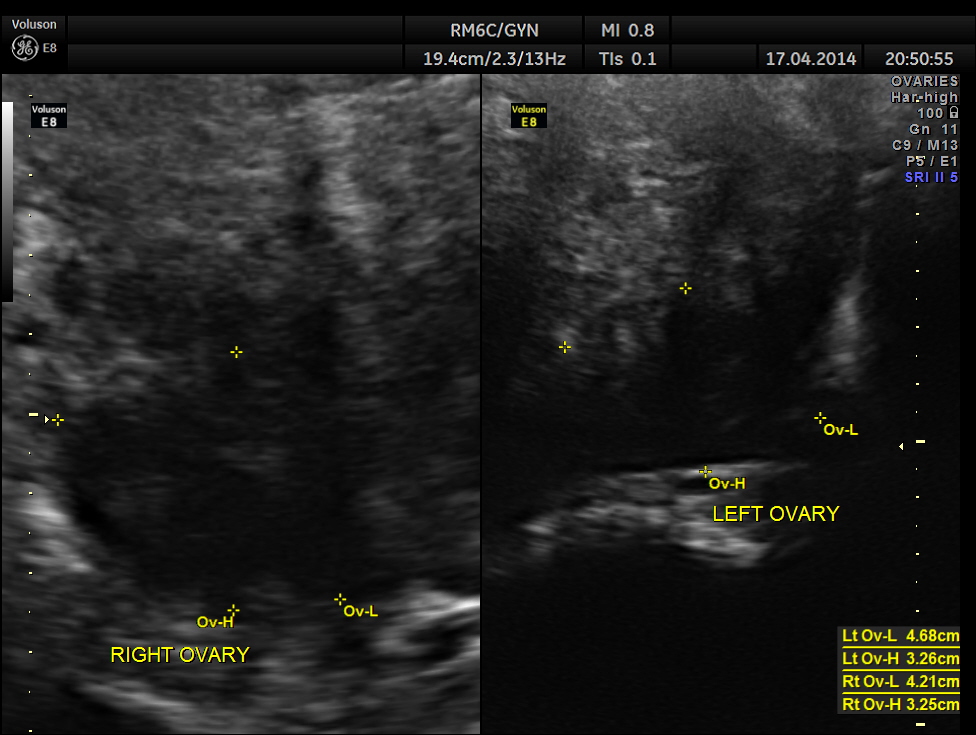

Uterus was massively enlarged and showed a large fibroid . Uterine texture also showed features of adenomyosis and endometrial thickening.

The ultrasound gave us a few inconclusive findings . Uterus was massively enlarged ; a large fibroid was seen ; adenomyosis was seen ; endometrium was thickened ; two large mass lesions were seen in the right upper quadrant and right lumbar region . But it was difficult to ascertain the origin of these extra uterine masses .